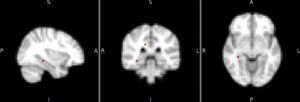

Diferencias de activación cerebral en reposo entre los gruposTrastorno bipolar I comparado con sujetos de controlEl patrón de activación cerebral de la red DMN en todos los sujetos con TBI frente a los controles mostró mayor activación en el grupo con TBI en el hipocampo (Hc) derecho y el cíngulo posterior derecho, con diferencia estadísticamente significativa (fig. 2). En esta misma red, la activación de otras áreas, como el cíngulo anterior, la CPF medial y el tálamo derecho, se mostró mayor en los sujetos con TBI, pero las diferencias no fueron estadísticamente significativas (tabla 2). En las otras tres redes (temporolímbica, frontal y salience), los sujetos con TBI no mostraron diferencias en el patrón de activación cerebral en comparación con los controles.

Diferencias de activación cerebral en las principales regiones cerebrales

| Red neuronal | Grupo de mayor activación | Región cerebral | Coordenadas atlas MNI_152 | p | ||

| x | y | z | ||||

| TBI frente a controles | ||||||

| DMN | TB | Hipocampo derecho | 34 | −34 | −8 | 0,049 |

| DMN | TB | Cíngulo posterior | 14 | −34 | −32 | 0,040 |

| DMN | TB | Cíngulo anterior | 6 | 14 | 32 | 0,08 |

| DMN | TB | Corteza frontomedial | 2 | 38 | −16 | 0,10 |

| DMN | TB | Tálamo derecho | 10 | −10 | 4 | 0,06 |

El aumento de la activación del Hc y el cíngulo posterior derecho fueron dentro de la red DMN, lo que se podría interpretar como un aumento de la activación de estas dos áreas con las otras regiones de la red, como el lóbulo temporal medial, la CPF medial, el precuneus y la corteza parietal medial, lateral e inferior4. La mayoría de las diferencias con tendencia a la significación estadística se encontraron también en esta misma red, y no en redes como la insular o la temporolímbica. Este hallazgo descriptivo en conjunto con estudios previos7,19 indica un papel relevante de la red DMN en el TBI, como también se ha propuesto en la depresión mayor y la esquizofrenia25,26.